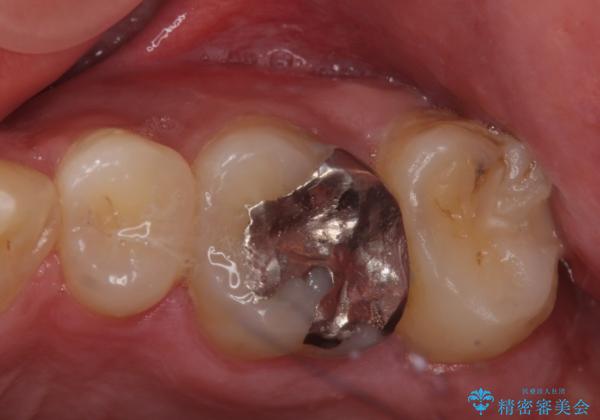

以上の提案より患者様に考えてもらい、①をご希望されたのでジルコニアクラウンによる治療を行った。

ご自身での歯ブラシによるセルフケアが大事になっていきます。

表面がツルツルした白い被せ物が入り、大変満足して頂けました。

銀の詰め物のやりかえも検討されています。